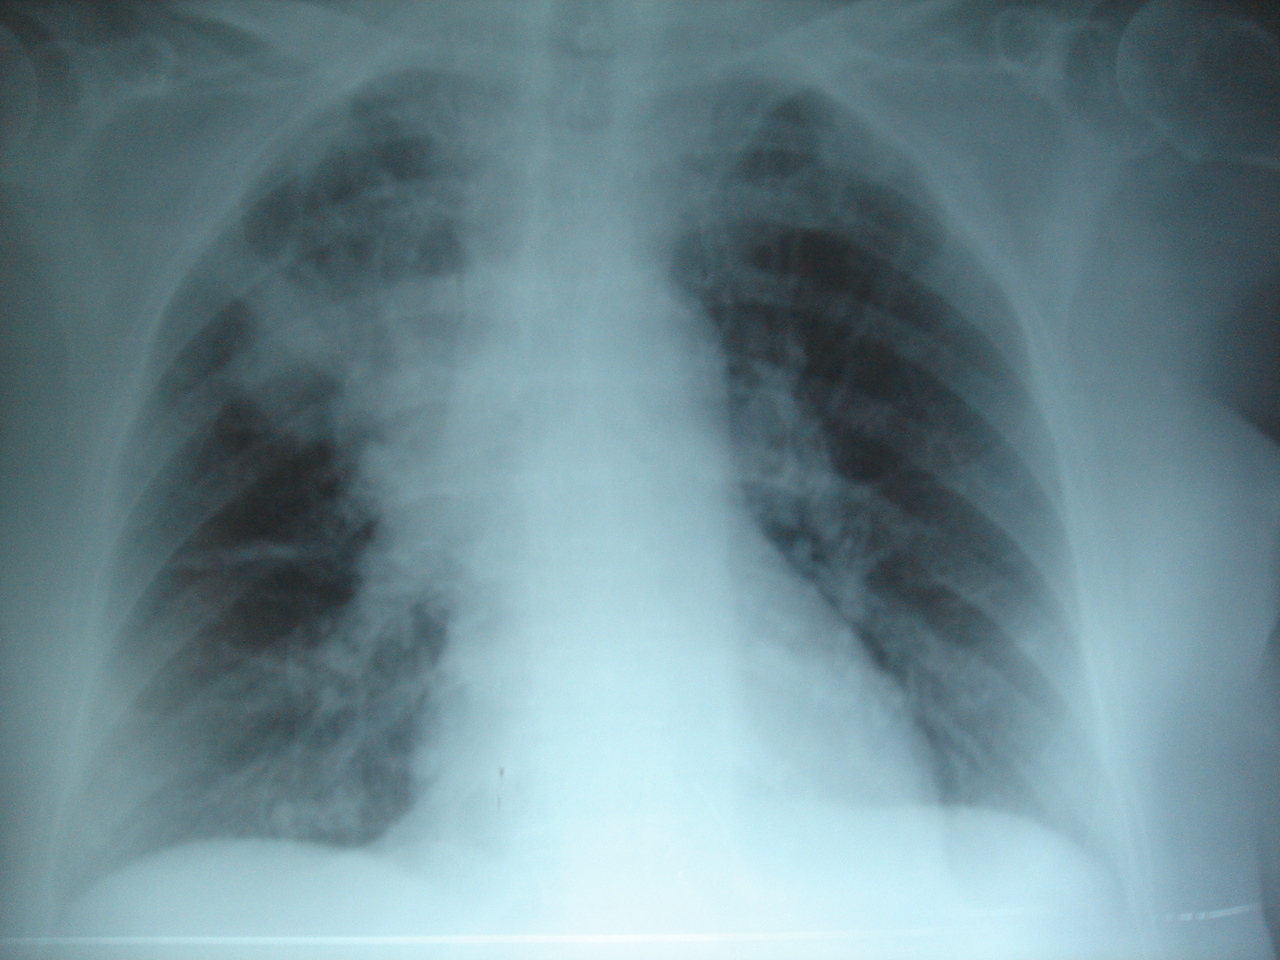

Чаще всего грипп приводит к геморрагической пневмонии, инфаркту и миокардиту. При диабете грипп может довести до комы. В группе риска дети, пожилые граждане, пациенты с ожирением, беременные, а также люди с хроническими патологиями.

Фото: No machine-readable source provided. Own work assumed (based on copyright claims), No machine-readable author provided. Joseaperez assumed (based on copyright claims), Creative Commons Attribution-Share Alike 3.0 Unported license.